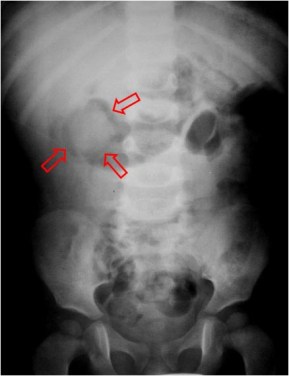

SIGNO DE LA MEDIA LUNA o SIGNO DEL MENISCO

Signo de invaginación intestinal en la radiografía simple de abdomen. Corresponde a la semiluna de gas intraluminal (flechas) que queda atrapado entre el asa invaginada y el asa invaginante.

También vemos una media luna en el enema opaco, esta vez formada por el bario que rellena el colon hasta el ángulo opaco. El defecto de repleción redondeado corresponde a la cabeza de la invaginación. Alrededor se acumula en bario con forma semilunar.

Hemos encontrado este signo con el nombre de Signo del menisco, y así aparece en el artículo de Jimena Mariano en la Revista argentina de radiología de 2009.(http://www.scielo.org.ar/pdf/rar/v73n2/v73n2a12.pdf)